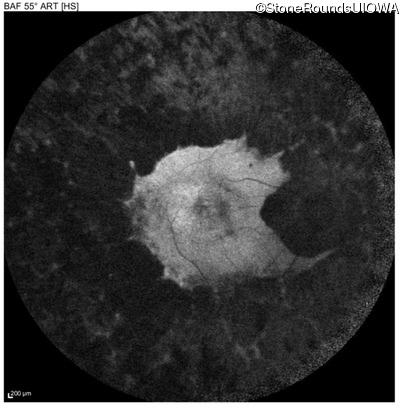

Age at visit: 46 years

This 46 year old man has had poor vision in dim light since age 2.

Diagnosis & molecular findings

AR Retinitis Pigmentosa SLC24A1 Met252 del2ggaAT Leu1052 del2ctTC AR